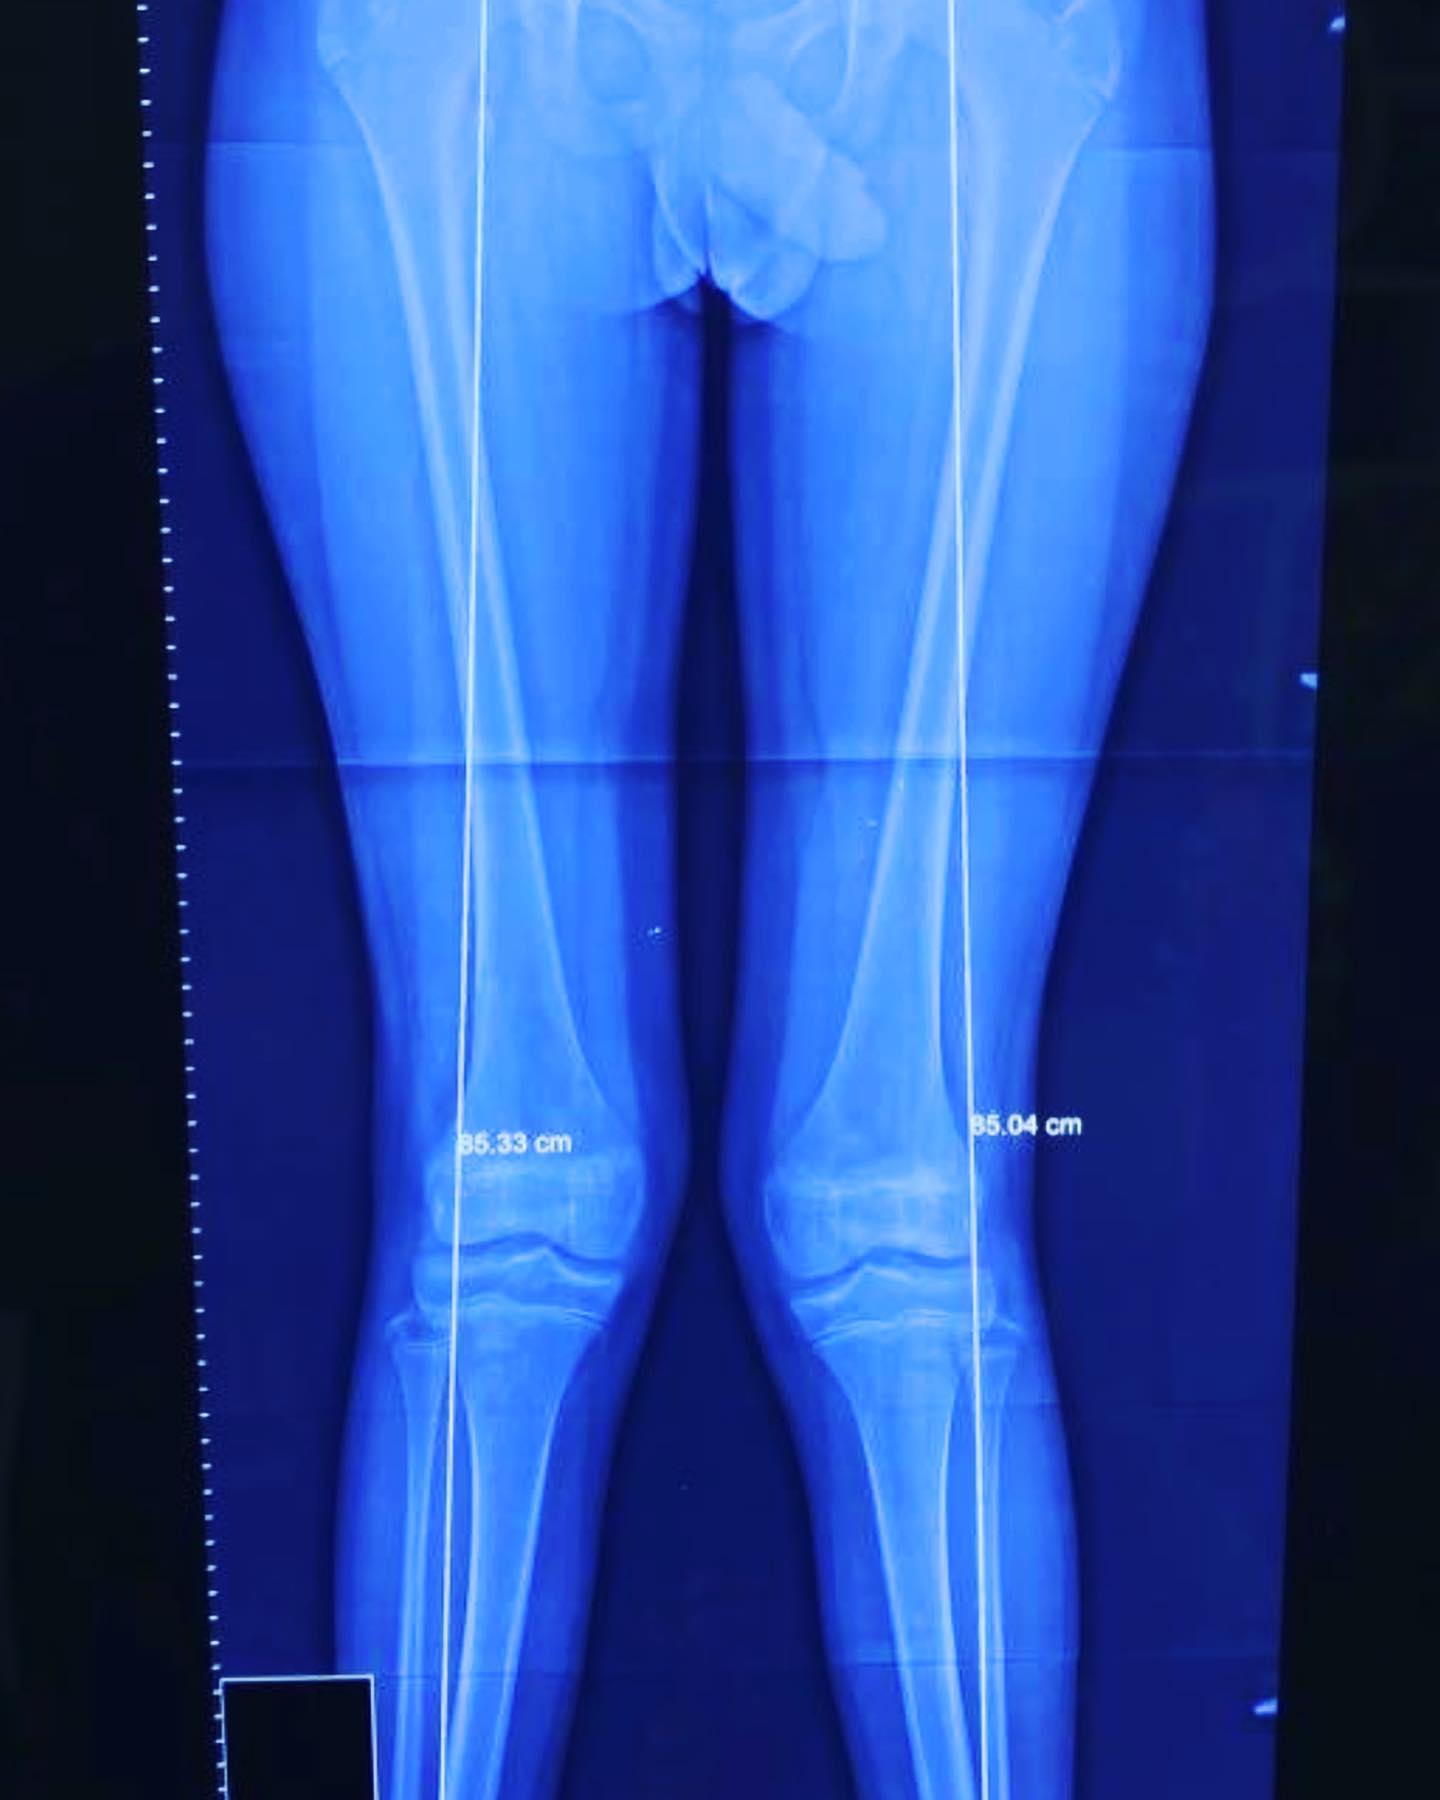

Rodillas en valgo

Él es mi paciente Isaac, de 13 años. Acudió a consulta hace 2 años por una deformidad en valgo de sus rodillas. Le realicé un tratamiento para corregir la deformidad y ahora lo doy de alta. #rodillasvalgas #correccióndeformidadesangulares